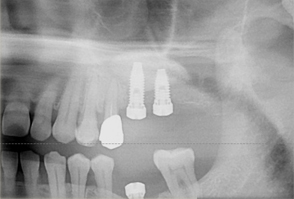

サイナスリフト

インプラント埋入前にサイナス部分にGBRを行い、骨が出来上がるのを待ってからインプラント治療を実施。

- 治療前の骨が足りていない状態

- サイナス部分にGBRを施し骨ができた状態

- 骨生成完了後インプラントを埋入し治療終了

- 主訴

- 上顎臼歯部の67欠損となり、上顎洞までの距離が不足したためインプラントの早期埋入が不可能であった

- 治療内容

- 上顎頬側よりラテラルウインドウ法で上顎洞底挙上術を行い2本のインプラントの埋入を行なった

- 治療費用

- 上顎洞底挙上術:150,000円(税別)、インプラント埋入1本:200,000円(税別)

- 治療期間

- 埋入手術までに6ヶ月